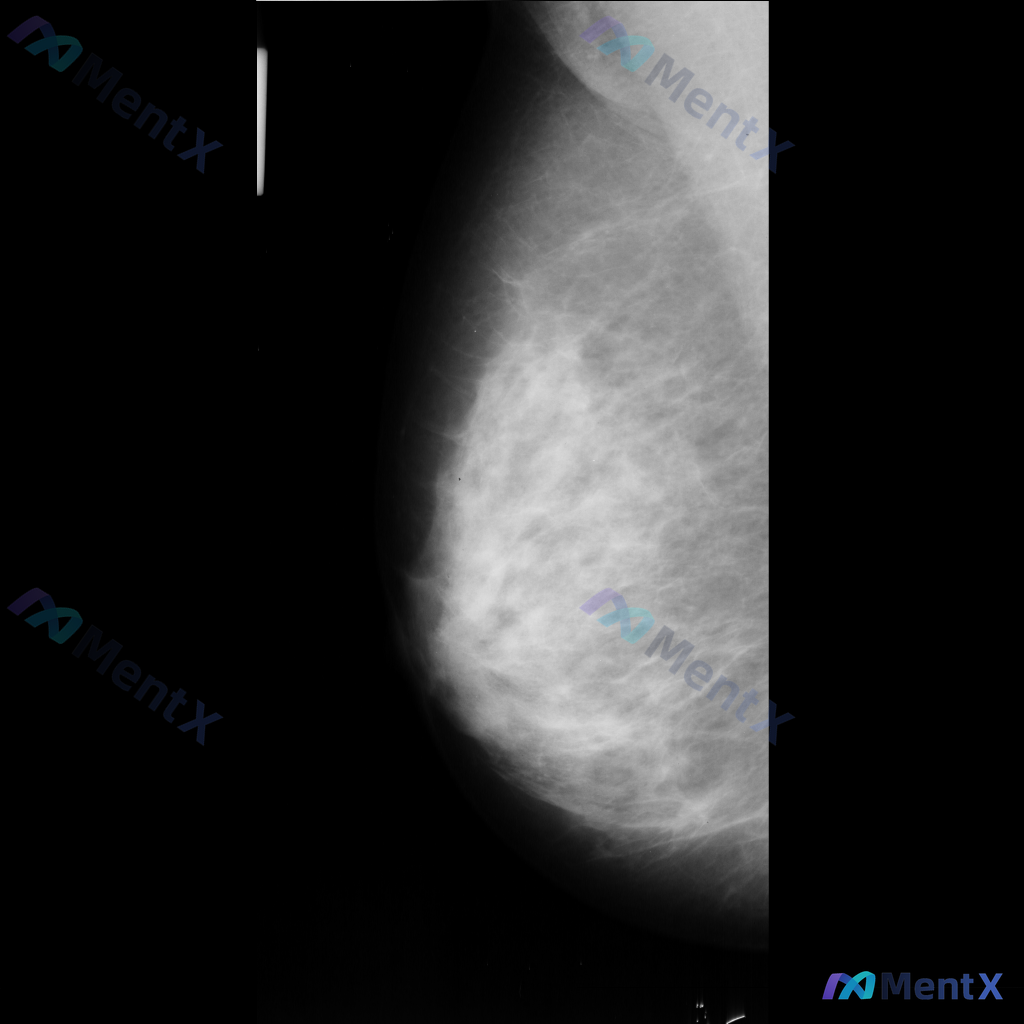

这张乳腺钼靶片的异常征象,你会先考虑哪种情况?

- 乳腺背景:腺体组织呈不均匀致密型,脂肪与腺体交错分布

- 主要异常:影像中央偏下方可见一区域性致密影,边界模糊,与周围腺体融合,性质待查

- 其他征象:提及可见散在的、数量极少的细小点状钙化,但无法详细描述形态和分布

目前只有这一张单侧片的信息,没有双侧对比、没有其他体位,也没有临床病史或超声等补充。